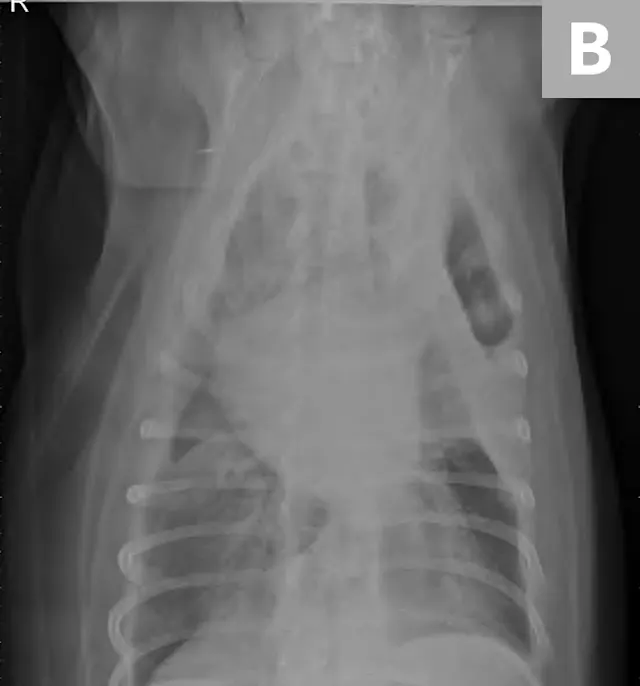

Right lateral thoracic radiographs revealed a large amount of fluid/soft tissue opacity obscuring the cardiac silhouette. Ventrodorsal radiographs showed increased soft tissue opacity in the left hemithorax, primarily in the cranial and middle lung fields. A mild interstitial pattern, a pleural fissure line, and border effacement of the heart were noted in the left hemithorax (Figure 1).

FIGURE 1A

Right lateral (A) and ventrodorsal (B) thoracic radiographs obtained prior to thoracocentesis demonstrating a mild interstitial pattern, moderate pleural effusion, soft tissue opacity in the left cranial and middle lung field, border effacement of the heart, and a pleural fissure line (arrows)

Radiography findings suggested a combination of pulmonary and pleural space disease. Differential diagnoses included pleural effusion (eg, hemothorax, pyothorax, chylothorax, hydrothorax, neoplasia) and pleural space mass or mass effect (eg, neoplasia, lung lobe consolidation or torsion, abscess/granuloma).